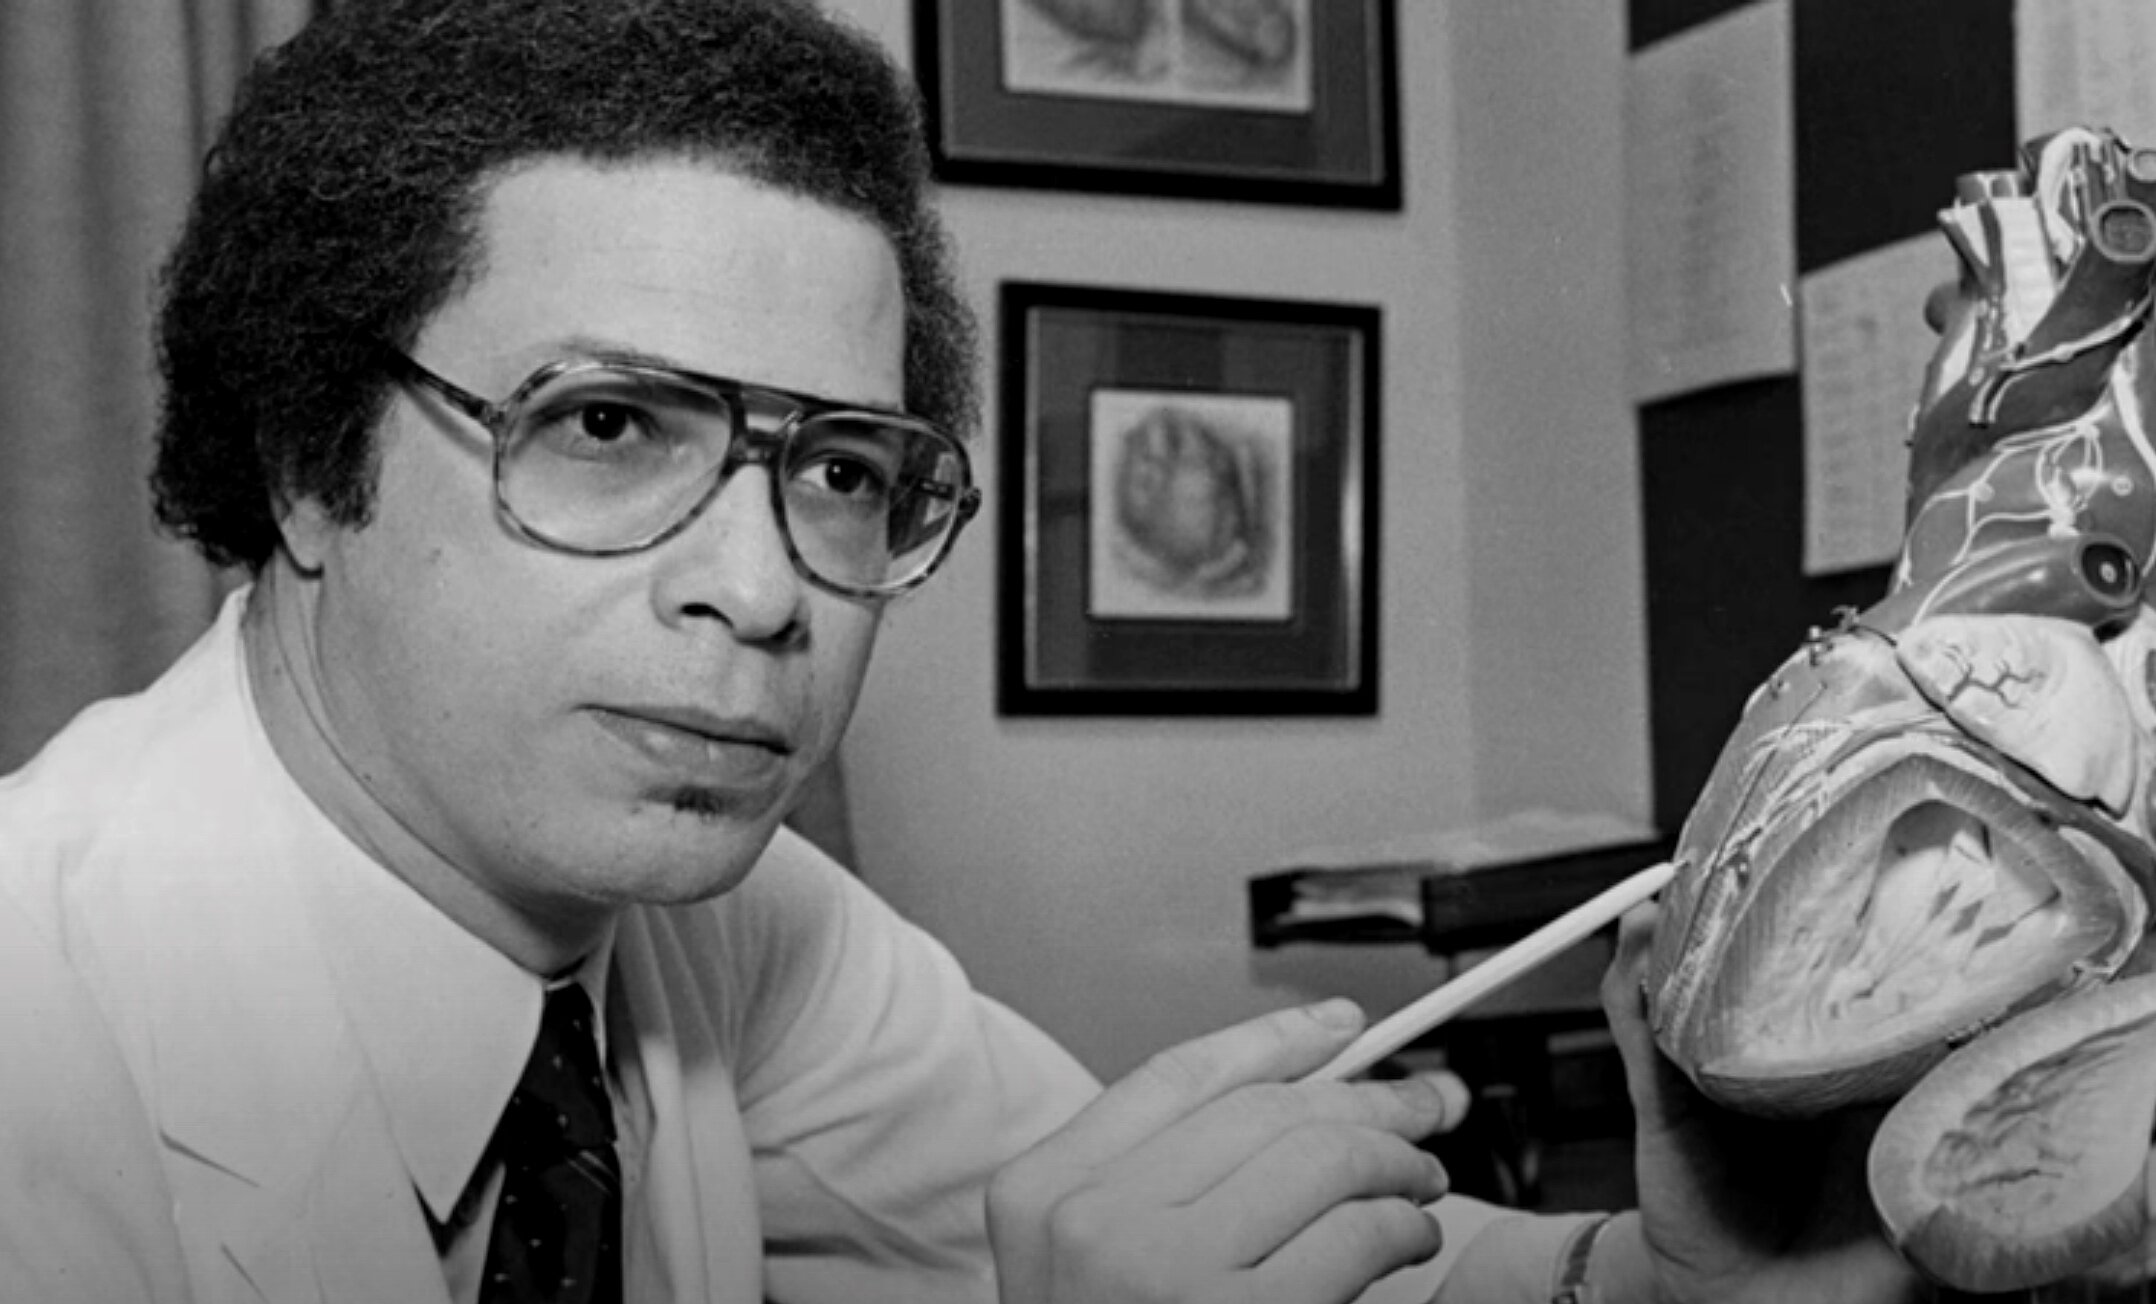

As supervisor of the surgical laboratories for over 35 years, Thomas went on to train a generation of surgeons at Johns Hopkins in the delicate techniques necessary for heart and lung operations. Notable among them was Hopkins’ first black cardiac resident Levi Watkins, Jr, who was a pioneer in the use of the automatic implantable defibrillator, performing the first human operation in 1980, after having first tested the device on dogs with Thomas in his lab.

Levi Watkins - bio from PBS documentary - Alabama -> Tennessee ... Vanderbilt -> Johns Hopkins

Re: Levi Watkins - Baltimore Sun - April 2015

Levi Watkins bio and videos - Johns Hopkins site

All Heart - article reviewing tenure of Dr. Levi Watkins at Johns Hopkins School of Medicine

“Her son, Dr. Levi Watkins, Jr., was the first African-American to graduate from Vanderbilt University and, in 1980, the first cardiac surgeon in the nation to perform a human implantation of the automatic implantable defibrillator.”

All Heart - 2013 article - brief bio of Dr. Levi Watkins, Jr.

Levi Watkins, 70, Dies - NYT obit - 4/16/15

Remembering Levi Watkins, Jr. - Vanderbilt U. article - 2015

Dr. Selwyn Vickers - Dean, UAB School of Medicine - honors Dr. Levi Watkins - Johns Hopkins Medicine - 2 min. video [re: Selwyn Vickers]